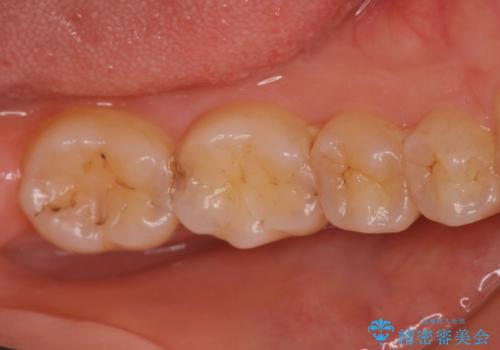

矯正終了後、詰め物を綺麗にしたい。セラミック治療

担当医 菊地俊介